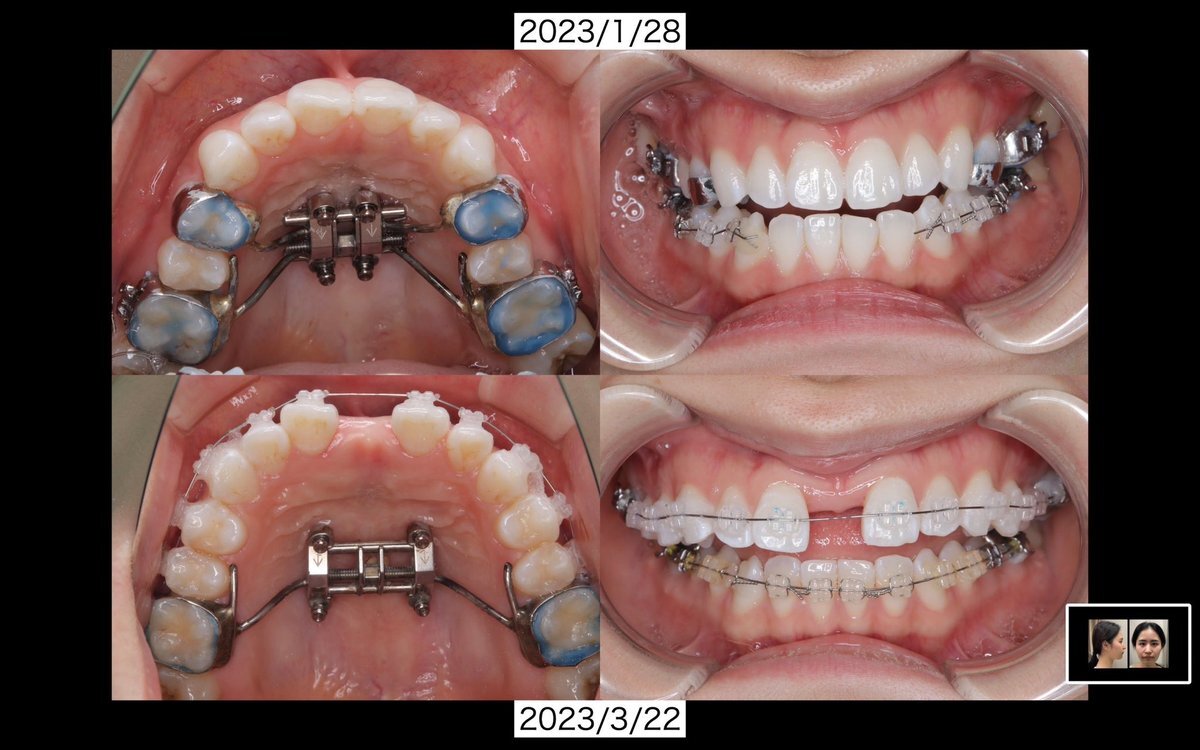

2023/3/22 上顎にワイヤー装着 これはワイヤー本来の目的というより、大事な予定があったから前歯が開いてるのが矯正のせいですってアピールする様につけたやつ! 柔らかいワイヤーで矯正感出す用💡 #MSE #急速拡大装着 #表側矯正 pic.x.com/y5cNrGe8hK

矯正ちゃん(MSE終了)@kyoseiganbaruru